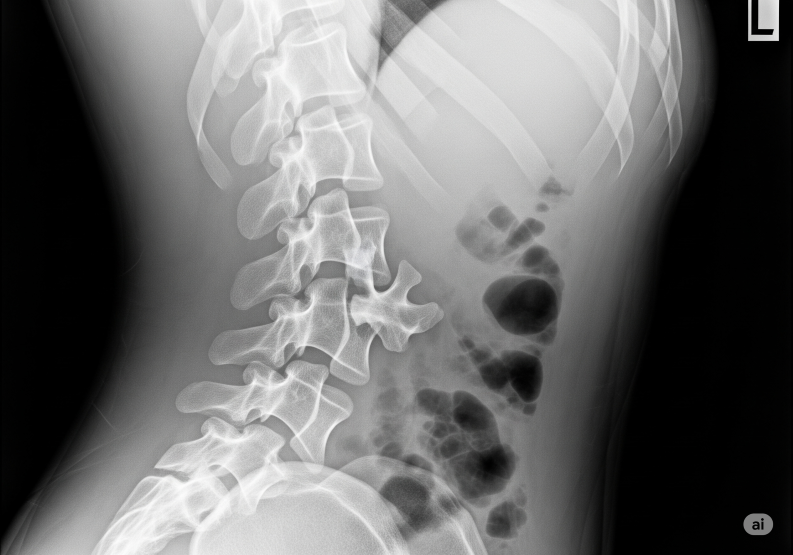

🩻 ThoracoLumbar Extension Fracture (TLEF)

A TLEF is a spinal fracture occurring in the thoracolumbar junction (T10–L2 region), usually due to extension injury (backward bending).

πŸ”Ή Diagnosis

. X-ray of thoracolumbar spine.

. CT scan β†’ to assess fracture pattern.

. MRI β†’ to check for spinal cord/nerve injury and ligament damage.